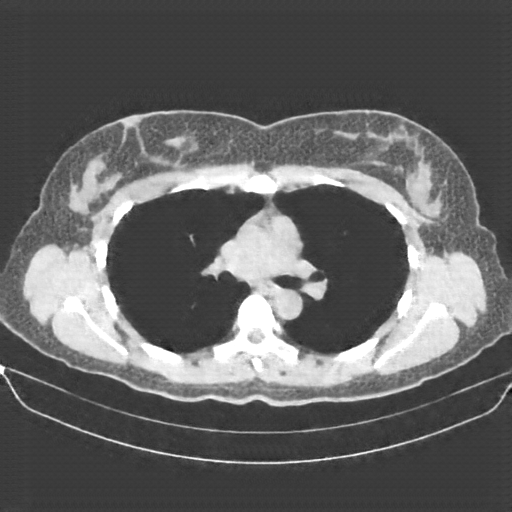

Generated VENOUS CT scan (A→B translation)

No window - Raw intensity values

Lung window (WL -600, WW 1500 β†’ Low βˆ’1350, High +150)

Mediastinum window (WL 40, WW 400 β†’ Low βˆ’160, High +240)